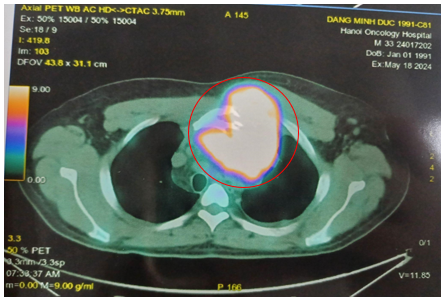

-         Hình ảnh chụp PET/CT đánh giá giai đoạn trước điều trị (tháng 5/2024)

·        Hạch nền cổ, thượng đòn 2 bên, lớn nhất ~ 28x18mm (SUVmax: 10.47).

·        Khối lớn ở trung thất trước, lệch trái kích thước ~84x109x90mm, phá hủy xương ức,cung trước xương sườn 3 trái, thành ngực trước trái, xâm lấn quai động mạch chủ (SUVmax: 17.88).

·        Vài hạch trung thất, lớn nhất 14x17mm (SUVmax: 3.17). Hạch rốn gan, hạch bẹn. Tăng nhẹ chuyển hóa FDG lan tỏa ở hệ thống xương.

Hình 2: Hình ảnh tăng chuyển hoá FDG ở nhiều vị trí khối lớn ở trung thất trước, hạch cả ở trên và dưới cơ hoành, tăng FDG lan tỏa hệ thống xương.

Hình 3: Khối lớn ở trung thất trước, lệch trái kích thước ~84x109x90mm, phá hủy xương ức